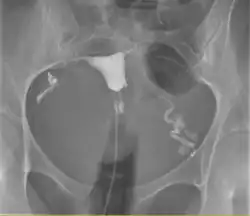

Uma histerossalpingograma normal. Observe o cateter entrando pela parte inferior da tela e o meio de contraste preenchendo a cavidade uterina (pequeno triângulo no centro).

Histerosalpingografia é um exame de raio-x do útero e das trompas uterinas, com a utilização de contraste iodado que é injetado no interior do útero através de uma cânula. Serve para diagnosticar malformações, doenças da cavidade uterina e do interior das trompas. Sua principal indicação está correlacionada com a infertilidade e é o melhor método[carece de fontes?] para diagnosticar obstrução das trompas.